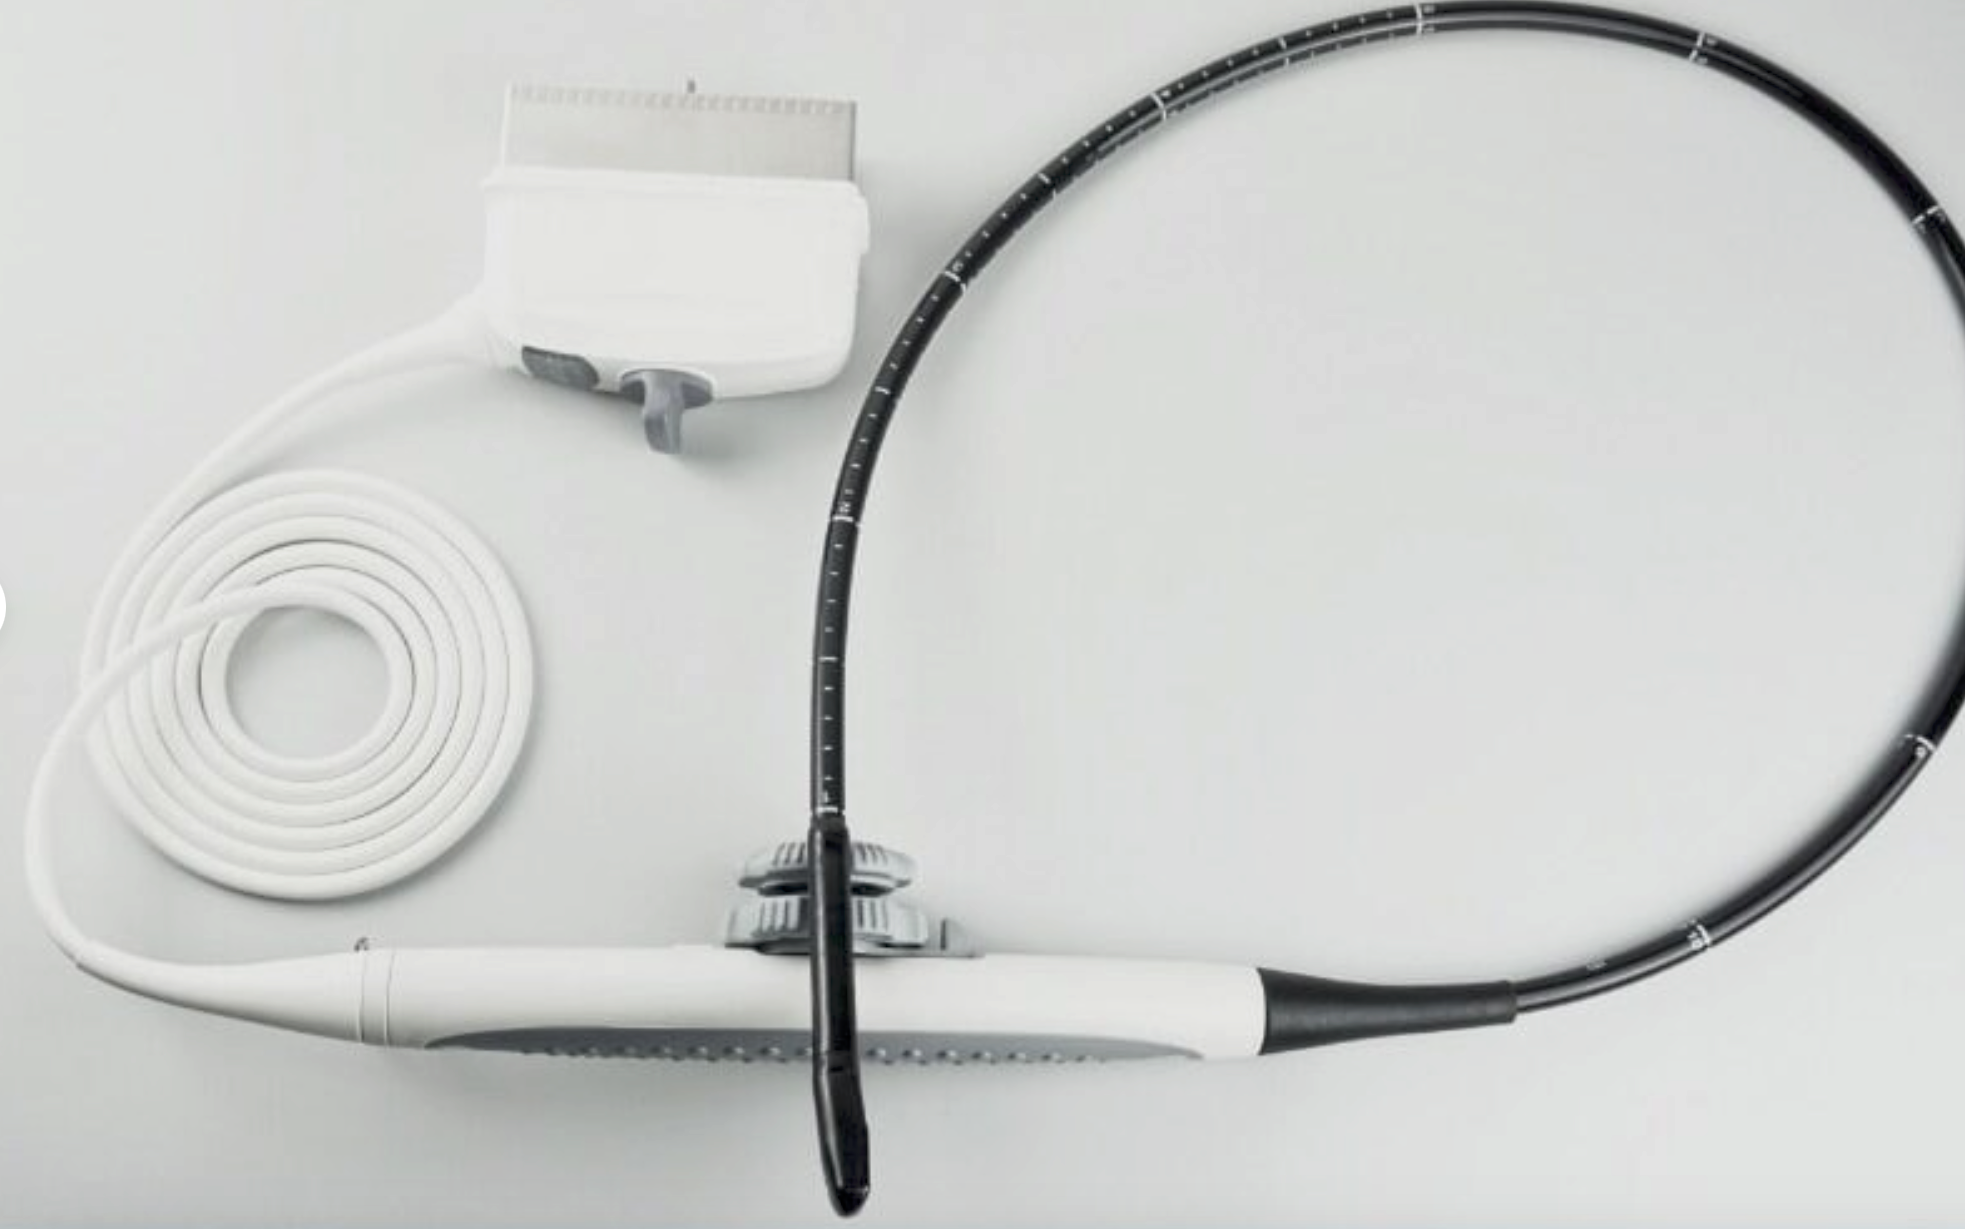

Probe: Convex Linear Transvaginal 3 Probe

Our portable ultrasound scanner is equipped with cutting-edge technology that improves diagnostic accuracy. With its convex linear transvaginal probe, it allows for detailed imaging of internal structures. The tool is designed to be user-friendly, meaning healthcare professionals can easily operate it without extensive training. Therefore, its advanced features can help in making quick and informed decisions in clinical settings, which is essential for patient care.

This portable ultrasound scanner is particularly beneficial in obstetrics and gynecology, as it provides clear and detailed images necessary for monitoring pregnancies and diagnosing conditions. Its transvaginal probe allows for a closer view of reproductive organs, which helps in identifying issues early on. Consequently, this versatility ensures that healthcare professionals can use it in various procedures, making it an essential tool in women’s health.